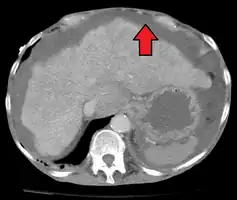

Ultrasound is routinely used in the evaluation of cirrhosis. It may show a small and nodular liver in advanced cirrhosis along with increased echogenicity with irregular appearing areas. Other liver findings suggestive of cirrhosis in imaging are an enlarged caudate lobe, widening of the fissures and enlargement of the spleen. An enlarged spleen (splenomegaly), which normally measures less than 11–12 cm in adults, can be seen and may suggest underlying portal hypertension. Ultrasound may also screen for hepatocellular carcinoma, portal hypertension, and Budd-Chiari syndrome (by assessing flow in the hepatic vein). An increased portal vein pulsatility is an indicator of cirrhosis, but may also be caused by an increased right atrial pressure.[33] Portal vein pulsatility can be quantified by pulsatility indices (PI), where an index above a certain cutoff indicates pathology:

Other tests performed in particular circumstances include abdominal CT and liver/bile duct MRI (MRCP).

Liver cirrhosis with ascites

Liver cirrhosis with ascites Liver cirrhosis as seen on a CT of the abdomen in transverse orientation

Liver cirrhosis as seen on a CT of the abdomen in transverse orientation caudate lobe hypertrophy in ultrasound due to cirrhosis